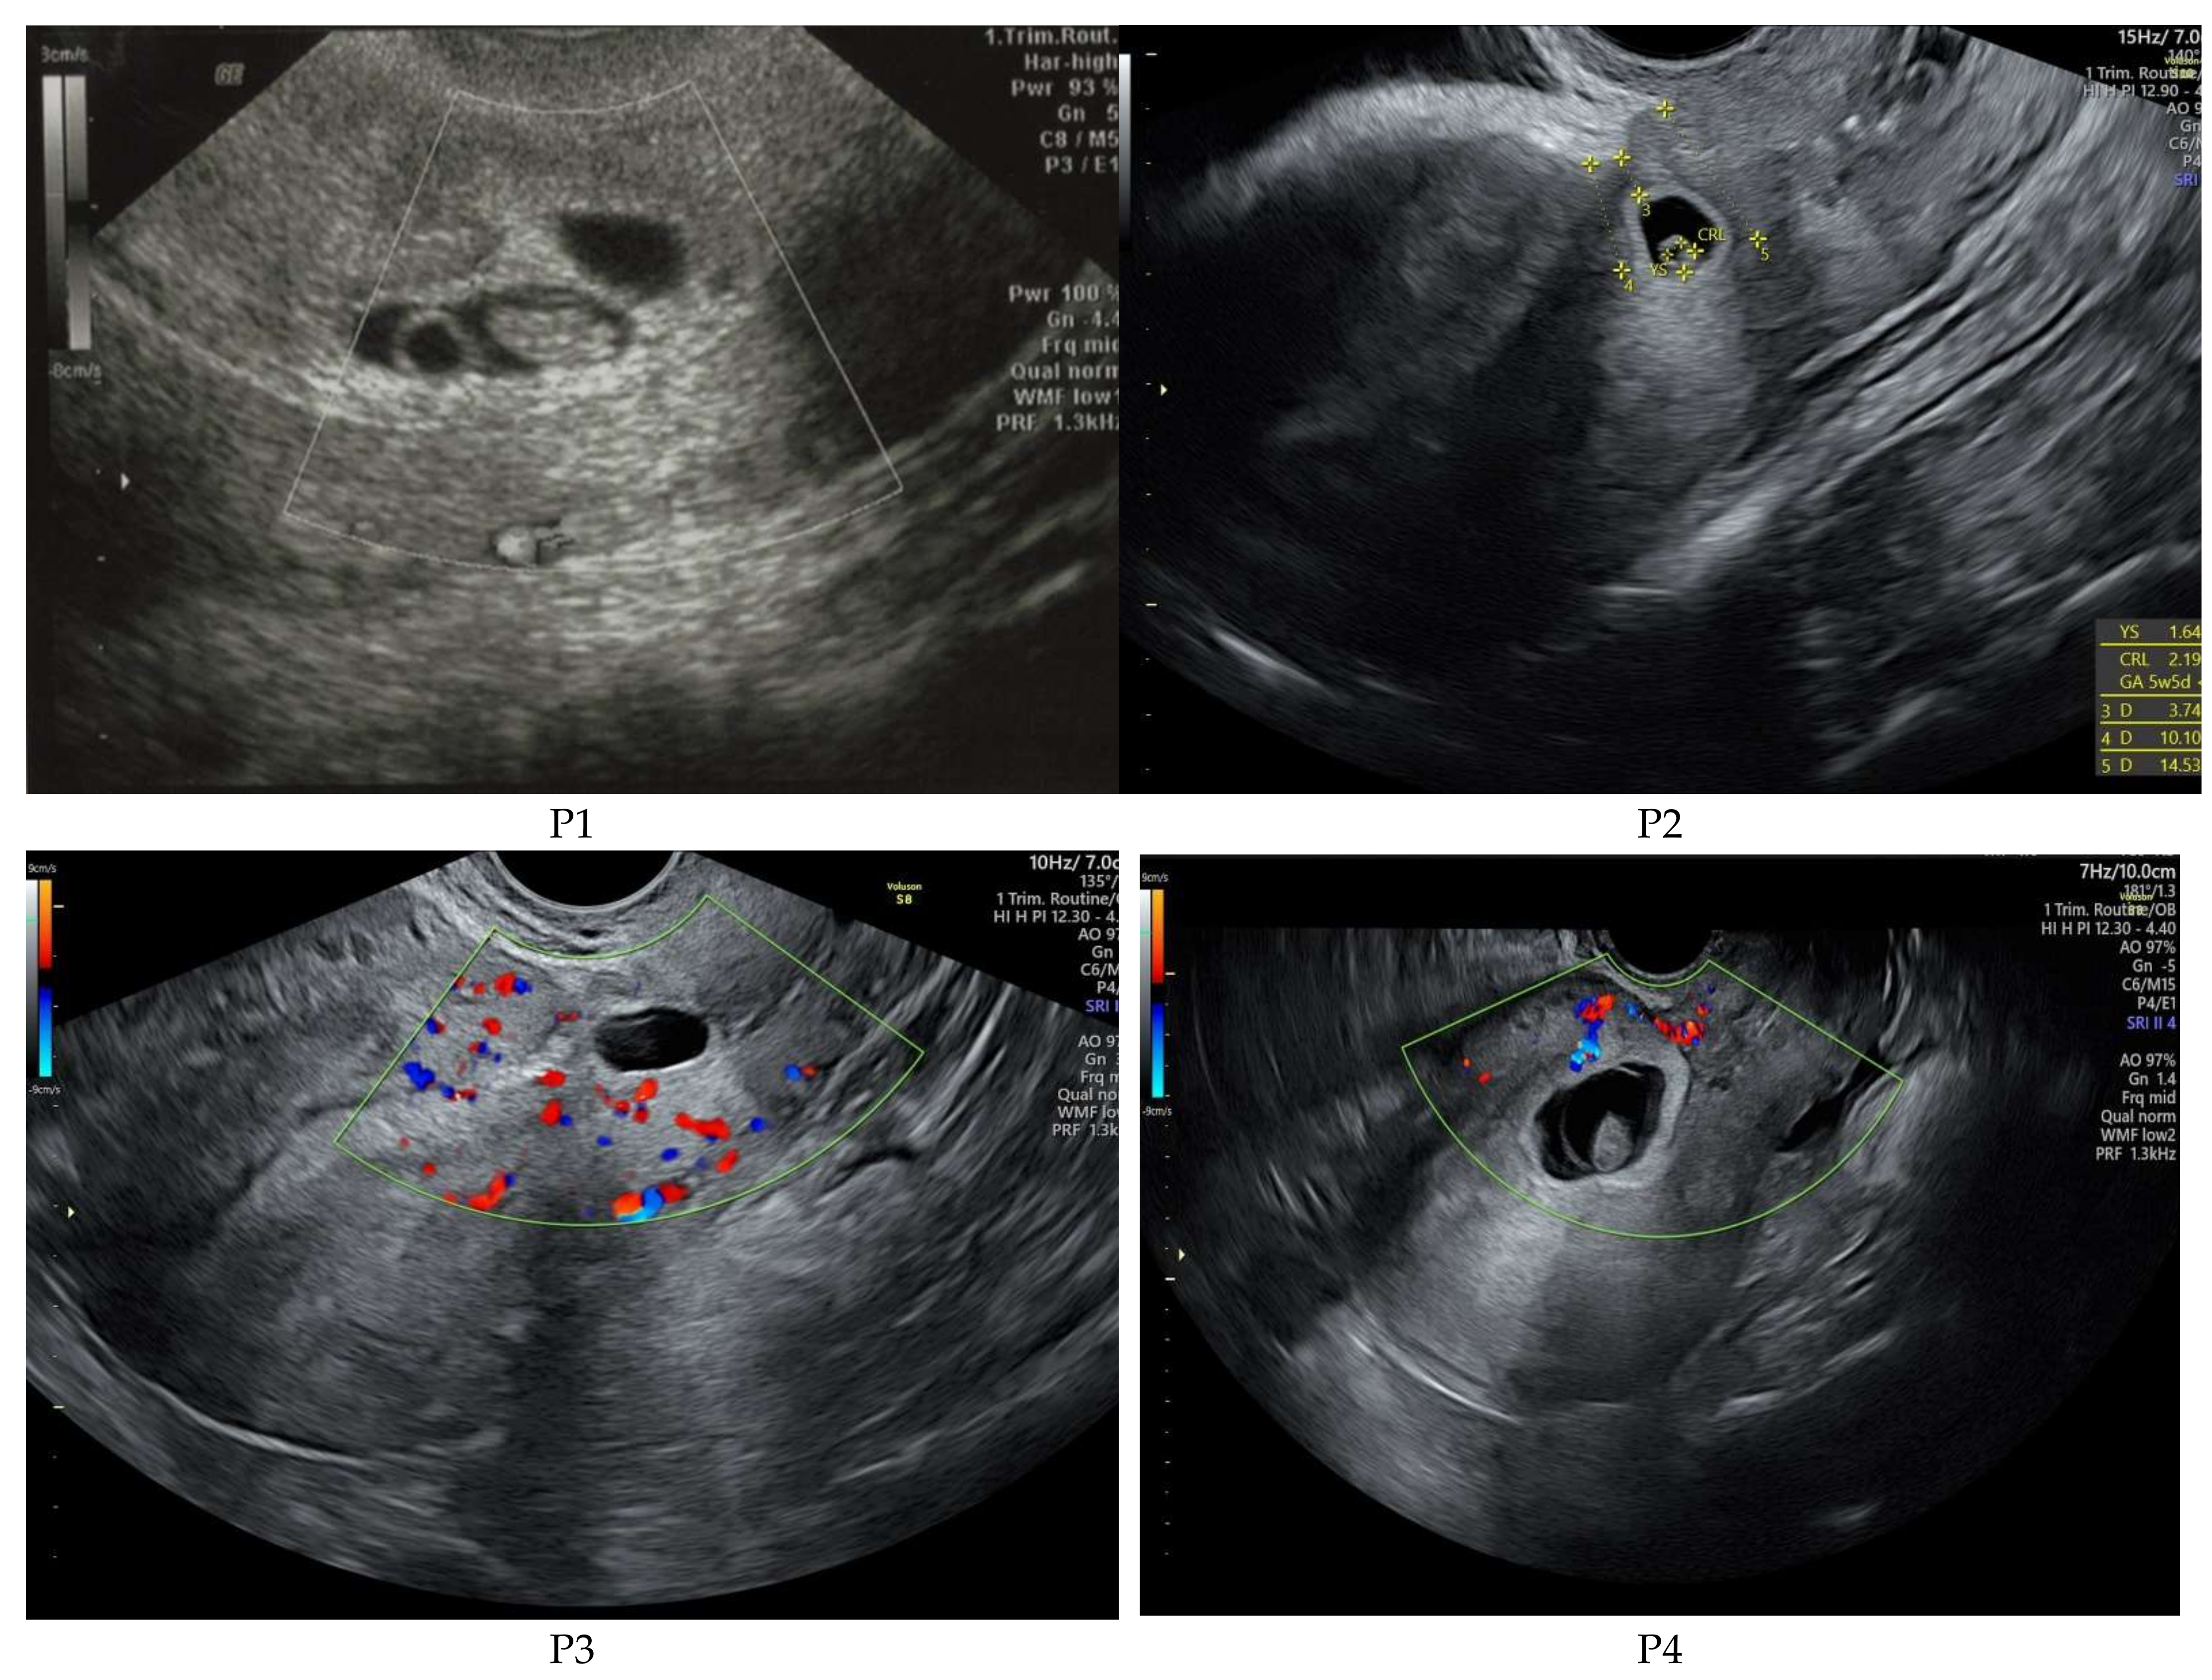

| Patient No | Peak bHCG Value | Gestational Age | CSP | Treatment Course | Outcome |

|---|---|---|---|---|---|

| P1 * | 99,999 | 7w + 1d | Type 1 | 1. Intramuscular methotrexate injection 2. Uterine artery embolization 3. Suction evacuation | No complications |

| P2 | 99,999 | 5w + 2d | Type 2 | 1. Intramuscular methotrexate injection 2. Uterine artery embolization 3. Suction evacuation | No complications |

| P3 | 62,309 | 7w + 2d | Type 2 | 1. Intramuscular methotrexate injection 2. Uterine artery embolization 3. Suction evacuation | No complications |

| P4 | 5938 | 5w + 5d | Type 1 | 1.Intramuscular methotrexate injection 2. Suction evacuation | No complications |

| P5 | 4579 | 5w + 6d | Type 2 | 1.Intramuscular methotrexate injection 2. Uterine artery embolization 3.Suction evacuation | No complications |

| P6 | 70,373 | 6w + 5d | Type 1 | 1. Intramuscular methotrexate injection 2. Uterine artery embolization 3. Suction evacuation | No complications |

| P7 | 46,317 | 6w + 2d | Type 2 | 1. Intramuscular methotrexate injection 2. Uterine artery embolization 3. Suction evacuation | No complications |

| Patient No | Residual Myometrium Thickness (mm) | Fetal Heartbeat | Vascularization | Crown-Rump Length (mm) | Gestational Sac Diameter (mm) | BMI |

|---|---|---|---|---|---|---|

| P1 * | 2 | absent | increased | 11 | 22/20 | 27.5 |

| P2 | 2.1 | absent | increased | Not measured | 11 | 22.5 |

| P3 | 1.6 | present | increased | 13 | 24 | 28.4 |

| P4 | 3.3 | absent | normal | 2 | 8 | 33.6 |

| P5 | 4 | absent | normal | Not measured | 8 | 29.4 |

| P6 | 3.8 | absent | increased | 4 | 23 | 19.7 |

| P7 | 3.5 | present | increased | 5 | 28 | 21 |